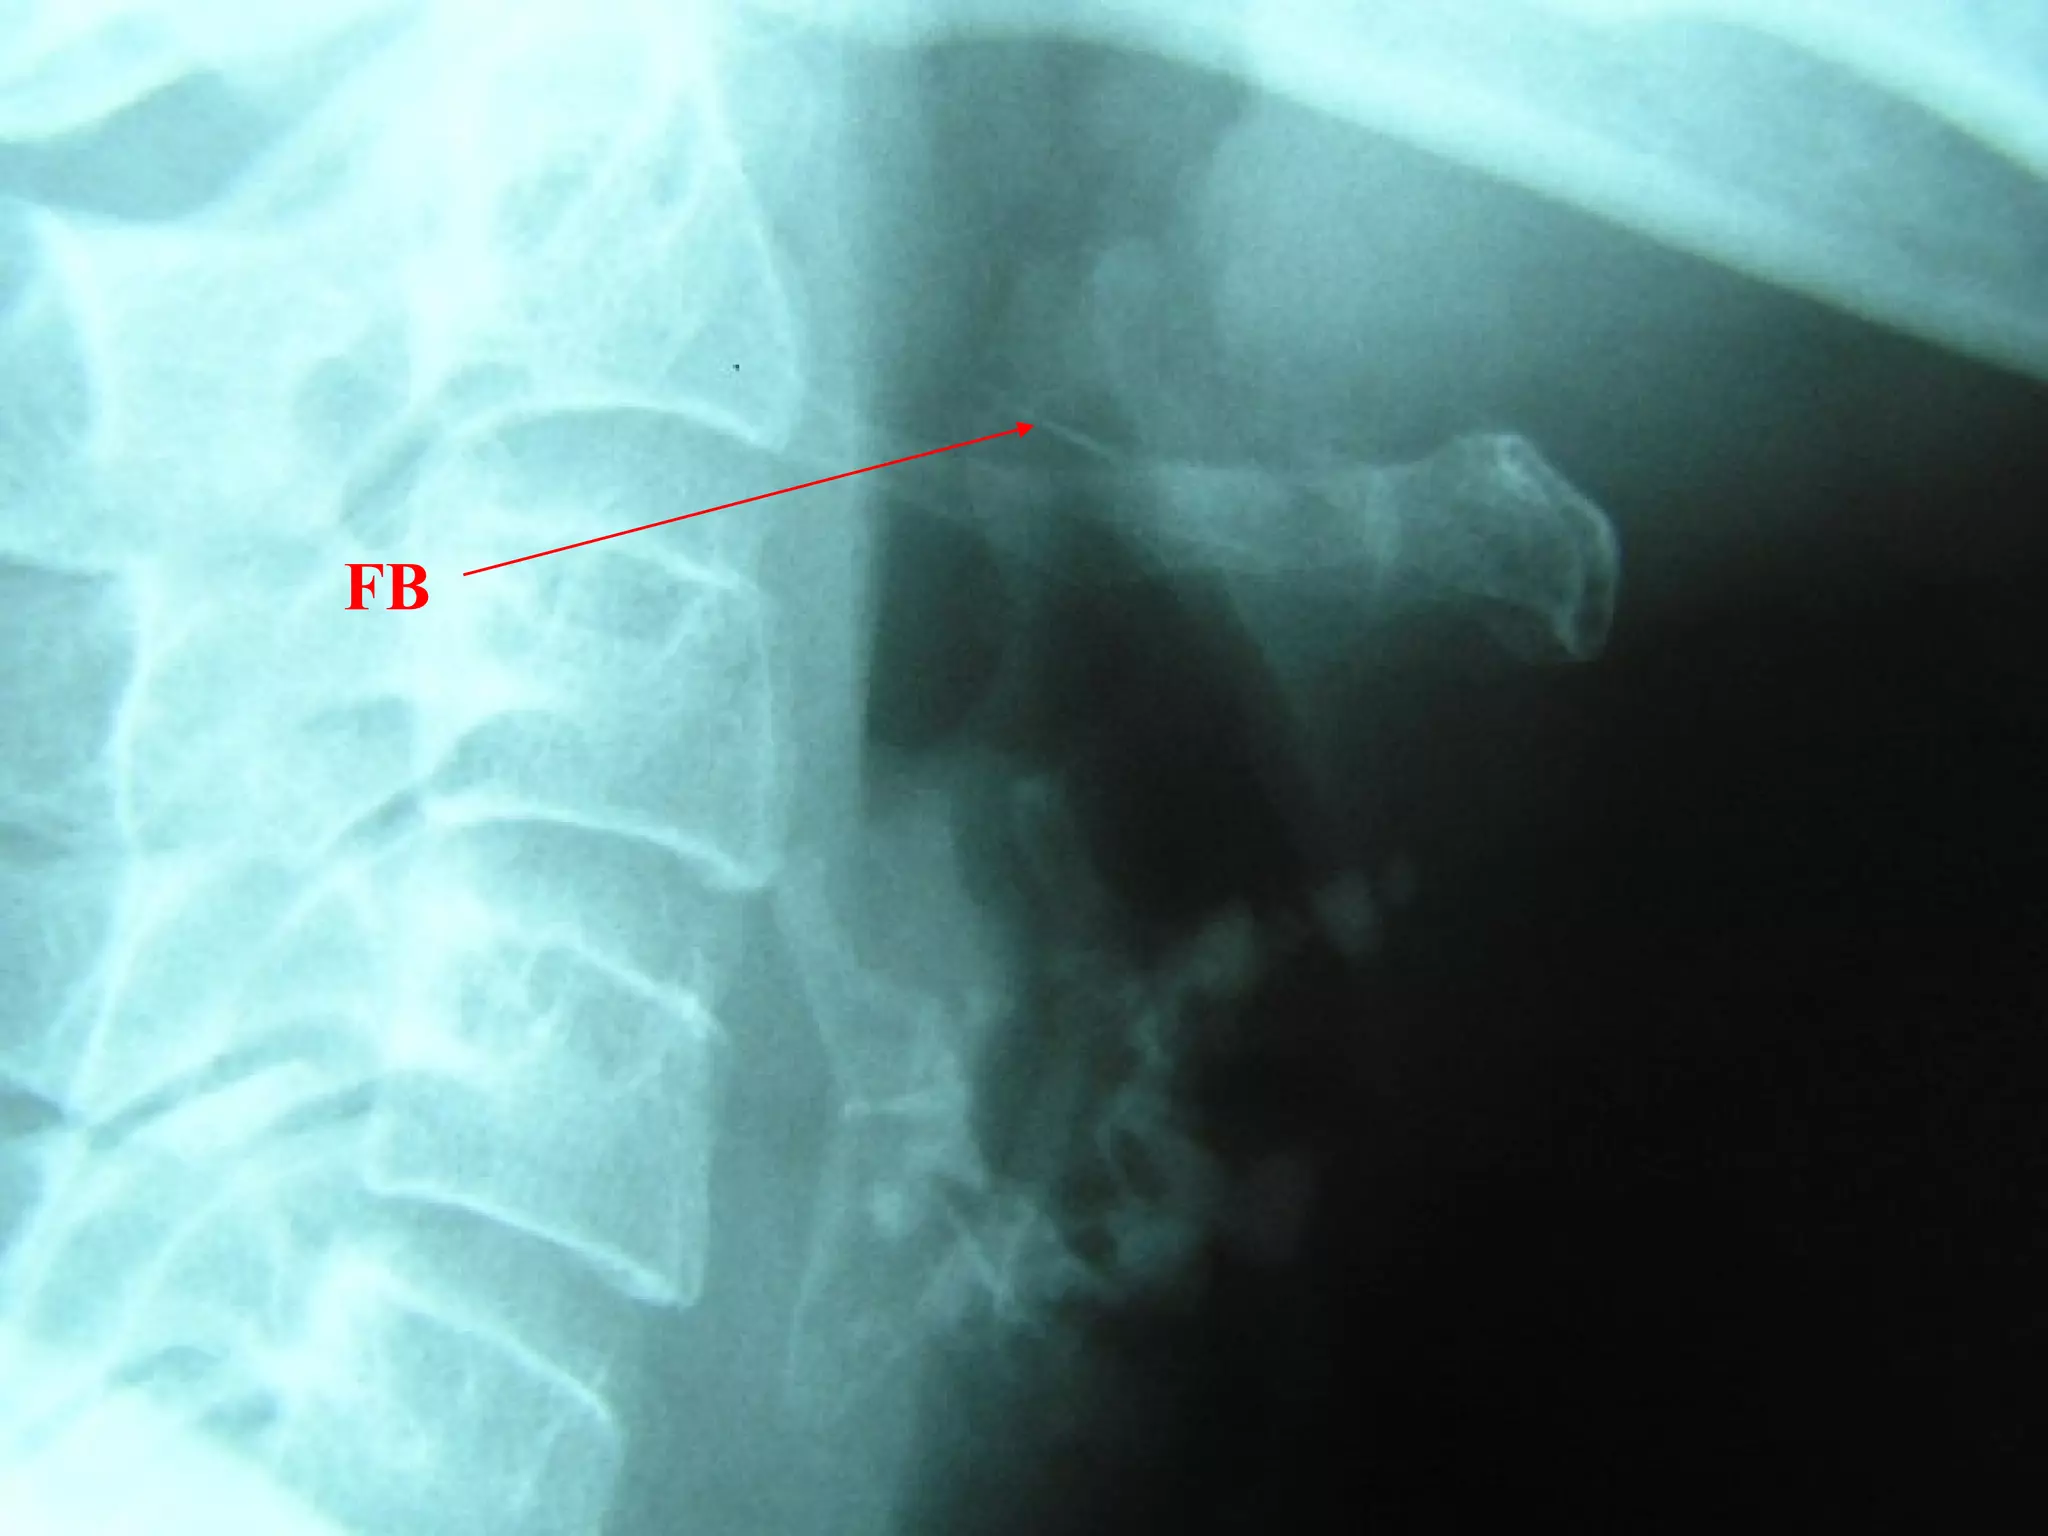

FB Throat - Investigations

Lateral neck XR

CXR

Barium swallow

CT scan – without contrast

Rigid oesophagoscopy

FB

Hyoid bone

Thyroid cartilage

Cricoid cartilage

Osteophyte

FB Throat

>50% of ingested FB cannot be found!

Discharge with symptomatic treatment

Cover with antibiotics if diabetic patient or

immunocompromised

FB advice

Chest pain, fever, increasing symptoms